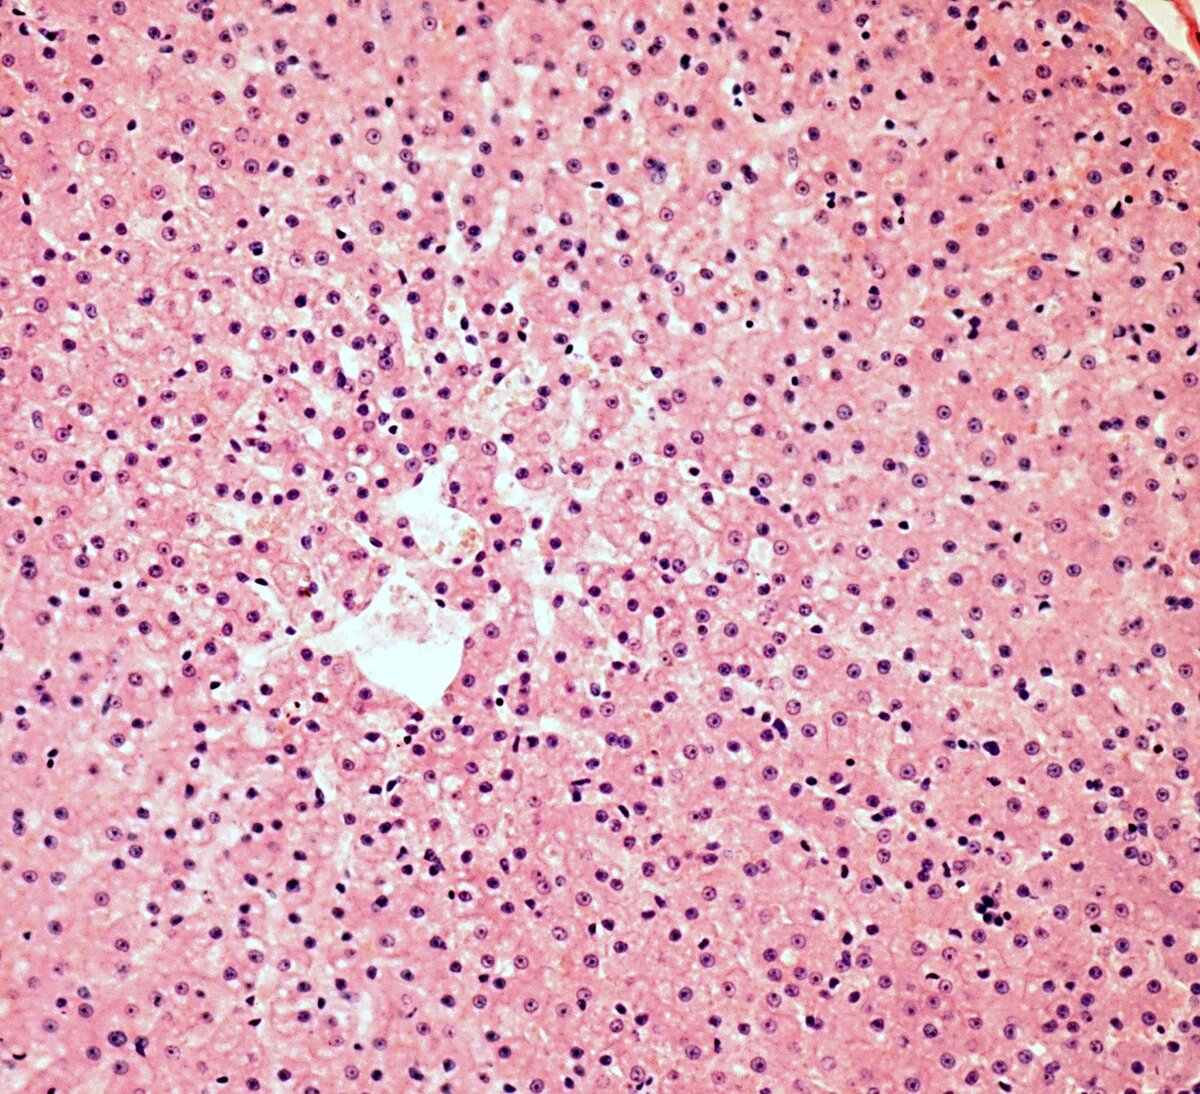

Нормальная микроструктура печени.

В задачу врача УЗД не входит установка диагноза, от него требуется правильное описание структуры органов, и в случае, если есть изменения, конкретизировать их, помочь клиницисту, т.е. лечащему врачу, определиться с диагнозом. По-этому необходимо к фразе "диффузные изменения печени" добавлять, какого характера изменения, наиболее часто это фраза "по типу стеатоза", или что-нибудь подобное, значительно реже "по типу цирроза"(очень серьёзное заболевание с неблагоприятным прогнозом), еще реже какой нибудь другой вариант диффузных изменений. Исходя из выше сказанного, когда в заключении есть только это словосочетание---диффузные изменения печени, то речь о стеатозе печени. Другими словами, это жировой гепатоз или жировая дистрофия печени (от греч. dys — нарушение и trophо— питаю) , или как стало модно называть, жировая болезнь печени(алкогольная или чаще неалкогольная). Суть ее в том, что в печени накапливается жир, причем как в клетках(гепатоцитах) так и в межклеточном пространстве.